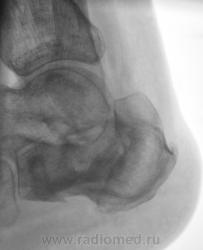

Пациент направлен на рентгенографию пяточных костей с диагнозом "остеомиелит". Год тому, пациент перенес перелом со значительным смещением отломков. Лечили... "как лечили". Сегодня прислали на рентгенографию с подозрением на остеомиелит.

Честно говоря интерпретировать такое не приходилось. Видно дефект кости и видно что он открывается за пределами кости. Так перелом сросся? Раз он как конь на параде, с чего тогда подозрение на остеомиелит?

В пяточной кости, определённо, не хватает костного фрагмента (может осколок удалён при операции); а в бугре пяточной кости - что-то "слишком светло" : как бы нейро-троф. расстройства

не спутать с лилизом (ОМ) - поднимать снимки п/е операции / снятия иммобилизации...

Пусть и дальше топает, как по мне - вариант комрессии с отличной консолидацией, а "псевдополость" - следствие этой самой компресии и оскольчатого перелома в сочетании с деформацией. Деструкции не видно!!!!!

А наружу ничего не открывается? ТИпа свищевого хода? На медиальной поверхности...

Ничего не открывается, да и пациент шагает, как конь "на параде".

Операции не было.

Видимо рассосался осколок. Только вот что за "дорожка" к наружной поверхности?

Операции не было. Был наложен ГИПС, и все...